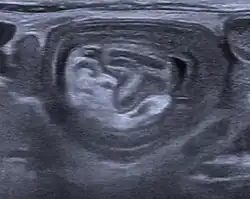

W badaniach diagnostycznycznych wykonywanych w trybie pilnym poza objawami klinicznymi podstawowym badaniem, wykorzystywanym w rozpoznaniu wgłobienia jest USG, w którym widoczny jest charakterystyczny obraz tarczy strzelniczej. Czułość tego badania wynosi około 98-100%[2]. W wątpliwych przypadkach wykonuje się zdjęcie przeglądowe jamy brzusznej, które wykazuje cechy niedrożności mechanicznej przewodu pokarmowego[6]. Inną metodą diagnostyczną jest wlew kontrastowy z zawiesiny barytowej, który może być równocześnie metodą leczenia wgłobienia[1][2].